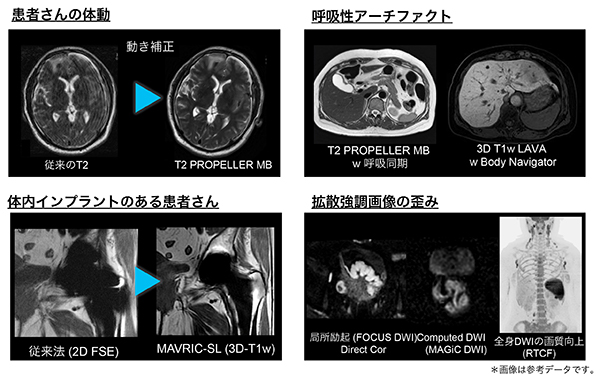

様々なアーチファクト抑制

・患者の体動や呼吸,金属インプラントなどによる,様々なアーチファクトを低減するアプリケーションを搭載可能です。

・「DISCO Star」による自由呼吸下での体幹部用ダイナミック撮像が可能になり,横隔膜同期による撮像法を含めて,患者の状態に合わせた最適な撮像ソリューションを提供します。